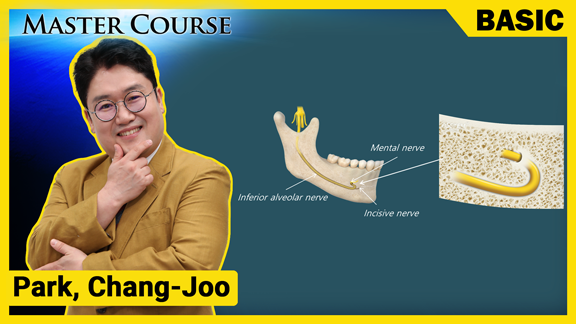

[BASIC] Anatomy for Implants

마스터코스

2022-08-03T00:00